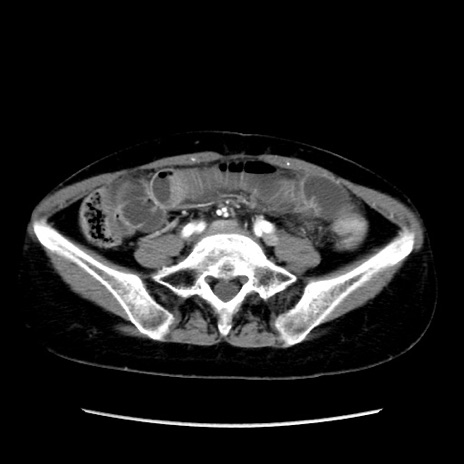

冠状断像